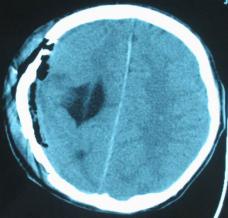

頭顱CT和MRI可見顱骨缺損區(qū)下方軟腦膜囊腫、腦軟化灶或腦室穿通畸形(圖2)。

圖2:①和②CT及骨窗相顯示右頂部顱骨缺損,其下方腦組織呈低密度改變;③-⑥MRI右頂局部顱骨缺如,腦組織輕度向外膨隆,右頂葉側(cè)腦室體部旁局部腦組織缺如,代之以囊性長T1、長T2信號。